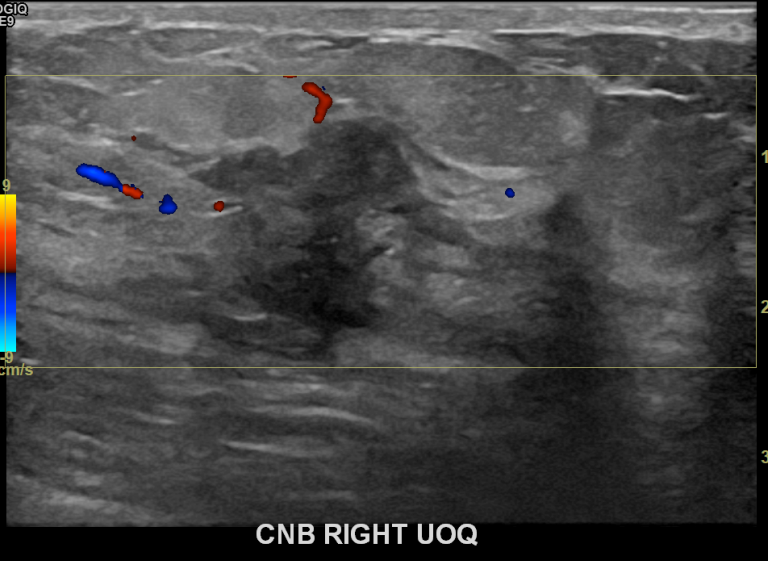

상기환자 우측멍울과 통증으로 내원하신  40대초반 여성분으로 의심스러운

우측혹 조직검사 시행해 상피내암으로 진단되었습니다